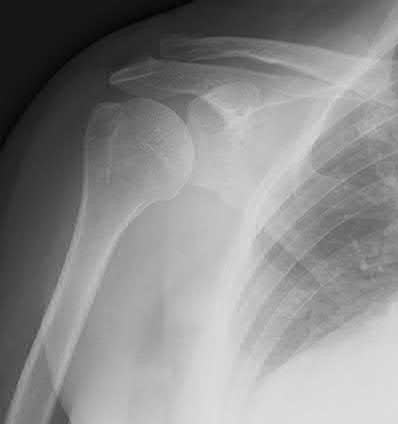

A 62-year-old right-hand-dominant school teacher sustains a mechanical fall at home and presents with right shoulder pain. Plain

radiographs of the right shoulder are pictured in Figures A and B. The patient asks you what she can expect in terms of recovery following this injury. Which of the following is the most appropriate statement?

This patient has a minimally displaced (1-part) proximal humerus fracture involving the humeral neck and greater tuberosity. This injury pattern is most commonly managed nonoperatively with the majority of patients returning to their baseline functional status by 1 year.

Proximal humerus fractures (PHF) can be classified by number of parts (Neer classification), with a part defined as a fracture fragment displaced > 1cm (> 5mm for greater tuberosity) or angulated > 45°. One-part PHF comprise ~80% of all PHF and are treated nonoperatively with a sling and early range of motion (ROM).

Figures A and B are the AP and axillary radiographs of the right shoulder, respectively, demonstrating a 1-part PHF involving the humeral neck and greater tuberosity.